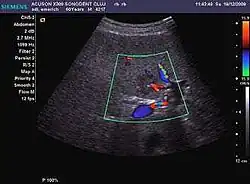

Dysplastic nodule (2D, CFM, CEUS). The nodule is well-defined with a size between 10– 20 mm, lacks vessels in CFM and CEUS exploration.

These lesions have various patterns (hypo or hyperechoic) with at least 1 cm diameter. They are hepatocytes with dysplastic changes, but without clear histological criteria for malignancy. They are divided into low-grade dysplastic nodules, where cellular atypia are mild and high-grade dysplastic nodules with moderate or severe cellular atypia, but without any established signs of malignancy. Occasionally, well-differentiated HCC foci can be identified in high-grade dysplastic nodules (appearance called "nodule in nodule") . Most authors accept the carcinogenesis process as a progressive transformation of DN from low-grade to high-grade and into HCC. The nodule's vasculature changes progressively, correlated with the degree of malignancy, and it is characterized by decrease until absence of portal venous input and by increase of arterial intratumoral input. Neoformation vessels occur with increasing degree of dysplasia. Arterial neovascularization is enhanced in a chaotic and explosive way, while normal, arterial and portal vasculature continues to decline. High-grade dysplastic nodules are hypovascularized both arterial and portal phases, while early HCC nodules may have similar arterial pattern with the surrounding parenchyma or exacerbated, and portal hypovascularization. In moderate or poorly differentiated HCC (classic HCC) tumor nutrition is performed only by neoformation vessels (abundant), the normal arterial and portal vasculature completely disappearing. This behavior of intratumoral vascularization is typical for HCC and is the key to imaging diagnosis.

B-mode ultrasonography is unable to distinguish between regenerative nodules and borderline lesions such as dysplastic nodules and even early HCC. Doppler examination also has a low sensitivity in differentiating dysplastic nodules from early HCC. Doppler signal may be absent in both regenerative and dysplastic nodules. Some authors indicate the presence of venous type Doppler flow which reflects the portal venous nutrition of the nodule as a characteristic feature of dysplastic nodules and early HCC (Minami & Kudo, 2010). Other authors noticed the presence of an arterial flow with small frequency variations and a normal resistivity index. On CEUS examination both RN and DN may have quite a variable enhancement pattern. Generally, both nodules enhances identically with the surrounding liver parenchyma after UCAs injection. Dysplastic nodules are hypovascular in the arterial phase. In case of highgrade dysplastic nodule sometimes a hypervascularization can be detected, but without associating "wash out" during portal and late CEUS phases. In these cases, biopsy may clarify the diagnosis.